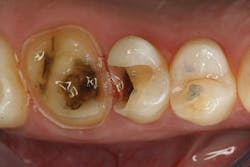

The clinical case in Figure 3 illustrates a patient who presented with a large, failing restoration containing cracks and decay. The patient was interested in an all-ceramic restoration. Occlusion was checked with articulating paper prior to treatment with a CAD/CAM restoration (figure 4). All previous restorative materials were removed from the tooth (figure 5). The tooth was restored using Grandio Core Dual Cure (Voco) build-up material (figure 6). A crown preparation was completed for a chairside CAD/CAM crown using the CEREC system (Dentsply-Sirona). The material of choice for this restoration was IPS e.max CAD (Ivoclar Vivadent), which is seen in Figure 7 after milling and in precrystallization form. The restoration was tried in and then polished, glazed, and placed in the oven for crystallization. The internal surface was then etched with 4.9% hydrofluoric acid, rinsed, and then coated with a silane coupler to create an optimal surface for bonding with the resin luting agent. The tooth was isolated and cleaned prior to etching. Once etched, the adhesive bonding agent (Futurabond U) was activated to mix the two liquids within the single-dose blister package. The blister seal was broken with the bonding agent brush and the adhesive was applied and agitated for 20 seconds. The adhesive was lightly dried for five seconds and then cured with an LED curing light for 10 seconds. A dual-cured adhesive resin luting agent (Bifix QM) was dispensed into the crown with its automix syringe (figure 8). The crown was seated and excess cement was removed after a two-second light cure. The tooth was then flossed and occlusion was checked (figure 9). The patient was very satisfied with the final result.

Figure 5: Teeth after all previous restorations have been removed